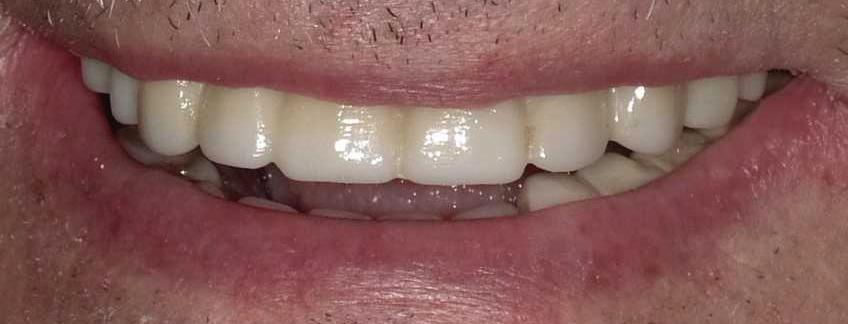

| What Is Cryotherapy? And How Can It Benefit You? | By Anthony T. Hardnett, DC 16 | All-On-Four Dental Implants | Submitted By Sivakumar Sreenivasan, DMD, MDS

Can just four implants replace all of the teeth on the top or the bottom of your mouth? Thanks to advances in dental implant technology, that answer is a resounding yes.

Tooth loss is extremely common among adults, especially as we age. Rather than living with the discomfort and hassles of dentures, many people are opting for what is called “all-onfour” dental implant restoration.

An implant is a small titanium screw

that fits inside your jawbone and replaces the root-part of a missing tooth. Minor surgery is required to insert the implants. Once the implant is in place, a crown is attached to give you a highly realisticlooking and functional prosthetic tooth. You do not need a dental implant for each and every one of your missing teeth. All you need is four precisely placed implants on the top of your mouth, and four on the bottom, to restore your full smile. That’s the beauty of the all-on-four. And because the implant is made of titanium, it has the unique ability to fuse to living bone and function as part of it. So eventually, the dental implant becomes part of the jawbone and serves as a strong, long-lasting foundation for your new teeth.

Besides ensuring that your implants are permanently fixed in place, this bone fusion has another important benefit: it prevents future bone loss in the jaw. This helps to maintain a more youthful facial structure – and better oral health. But perhaps the biggest